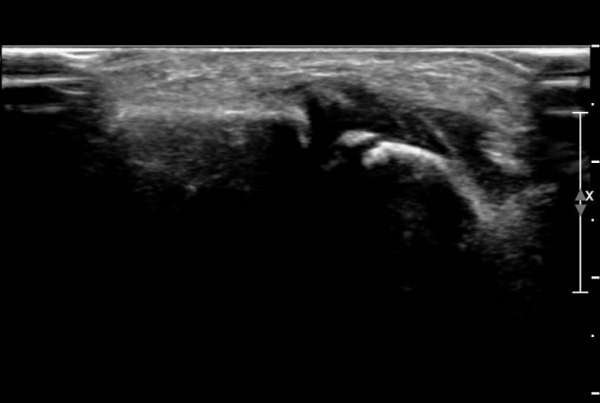

¹Ý´ëÃø  ¾Õ°æ°ñºñ°ñÀδë Á¾´Ü¸é°Ë»ç¿¡¼­  Àδ밡  °í¿¡ÄÚ·Î Á¤»óÀûÀÎ ¸ð½ÀÀ» º¸ÀÓ(»çÁø 7).